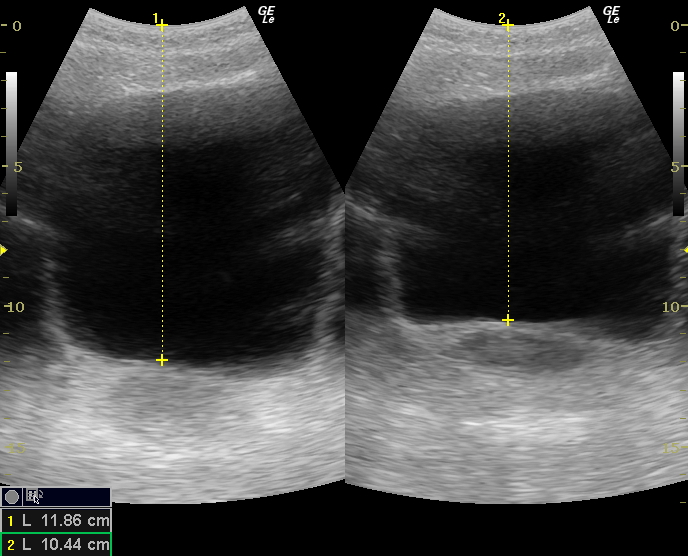

私自身、エコー検査で最大1.42cmの引き上げを確認しました(下記写真参照)。

この「確かな感覚」があるからこそ、自信を持って指導ができるのです。